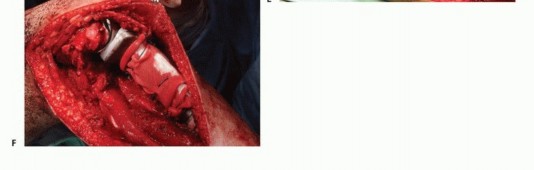

دور سديلة العضلة التوأمية الإنسية (Gastrocnemius Rotational Flap)

يُعد استخدام سديلة العضلة التوأمية الإنسية (عضلة الساق) عاملاً رئيسياً في تحقيق تغطية كافية للأنسجة الرخوة للطرف الصناعي واستعادة وظيفة آلية المد. تُنقل هذه العضلة لتدور إلى الأمام لتغطية الطرف الصناعي، مما يقلل بشكل كبير من خطر العدوى ومضاعفات الجروح، وهو ما كان يمثل تحدياً كبيراً في الماضي. يؤكد الأستاذ الدكتور محمد هطيف على أن هذه التقنية أصبحت إجراءً روتينياً وموثوقاً لضمان تغطية الطرف الصناعي وتقليل معدل العدوى ونخر السديلة والبتر الثانوي.

تفاصيل الإجراء الجراحي للحفاظ على الطرف

تُعد جراحة الحفاظ على الطرف في أورام قصبة الساق القريبة إجراءً معقداً يتطلب خبرة جراحية عالية وتخطيطاً دقيقاً. يقوم الأستاذ الدكتور محمد هطيف بتطبيق أحدث التقنيات لضمان استئصال الورم بشكل كامل وإعادة بناء الطرف بأمان وفعالية. تتضمن الجراحة ثلاث خطوات رئيسية:

- استئصال الورم: إزالة الجزء المصاب من قصبة الساق والأنسجة المحيطة به مع هامش أمان كافٍ.

- إعادة بناء العيب الهيكلي ومفصل الركبة: زرع طرف صناعي أو طعم عظمي لاستبدال الجزء المستأصل.

- إعادة بناء آلية المد وتغطية الطرف الصناعي بالأنسجة الرخوة: استخدام سديلة العضلة التوأمية لضمان التغطية والحفاظ على وظيفة الركبة.

استكشاف الحفرة المأبضية والحزمة الوعائية

يجب استكشاف تفرع الشريان المأبضي مبكراً لتحديد ما إذا كان الورم قابلاً للجراحة، خاصة إذا كانت مكوناته في الأنسجة الرخوة تمتد خلفياً. إذا لم يكن هناك امتداد خلفي، يتم تعريض الفراغ المأبضي والتفرع عن طريق فصل العضلة التوأمية الإنسية وشق العضلة النعلية. يمكن تحديد الشريان المأبضي بسهولة وتتبعه بعيداً حول العضلة المأبضية. يجب توخي الحذر لتحديد وحماية جميع الفروع الوعائية الرئيسية.